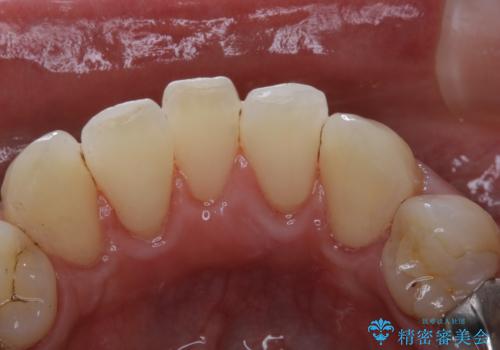

歯の表面に、茶色く色が残っている所がありますが、これは詰め物の変色の所と、虫歯になっている所です。以前に、CR(コンポジットレジン)による虫歯治療がされています。

CRは経年的劣化や、着色してしまうことがあります。PMTCでクリーニングを行うと、古いCRが目立つことがあるため、気になる際は詰め替えを行います。

茶色くなっている部分が、着色なのか、劣化なのか、虫歯によるものなのかは判別が難しいことがあります。そのため、定期的にPMTCを行うことで状態の確認が的確に行えます。

また、治療が開始される前などにも、全体的にクリーニングを行いご自身本来の歯の色、状態を精密に確認することが大切です。